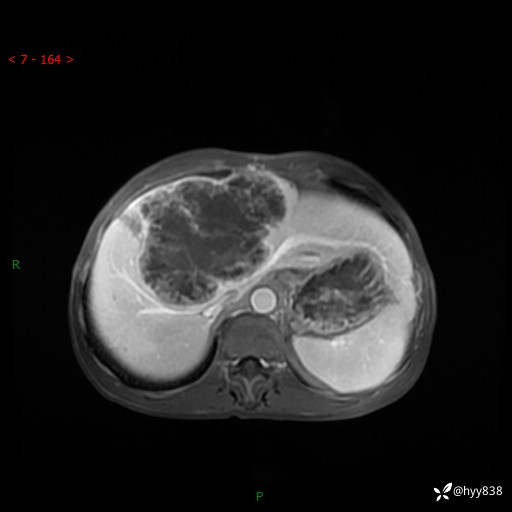

【患者信息】:58岁/男

【主诉】:发现肝占位2天

【现病史及既往史】:患者2天前于当地市第五医院查上腹部磁共振提示:肝脏S4段占位性病变,肝ca可能,胆囊结石,腹膜后多发肿大淋巴结,无剑突下及右上腹疼痛不适,无明显反酸、嗳气,无畏寒、头晕、头痛,无尿频、尿急、尿痛等不适,今为求进一步治疗特来我院就诊,门诊以“肝占位”收住我科。 患者病程中精神、睡眠、饮食尚可,大小便正常、体力体重无明显变化

【检查】:肝脏MRI】平扫+增强